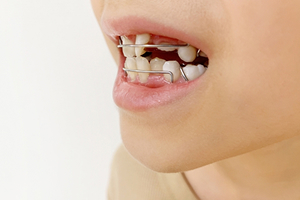

1.床矯正

床矯正は、取り外し可能な装置を用いて顎の発育を助けながら、歯列のスペースを広げる矯正方法です。顎のスペース不足を解消することで、歯がきれいに並ぶ土台を作ります。痛みが比較的少なく、装着も簡単なため小さなお子さまでも無理なく使えます。自宅で取り外せるので、食事や歯磨きもスムーズに行えます。